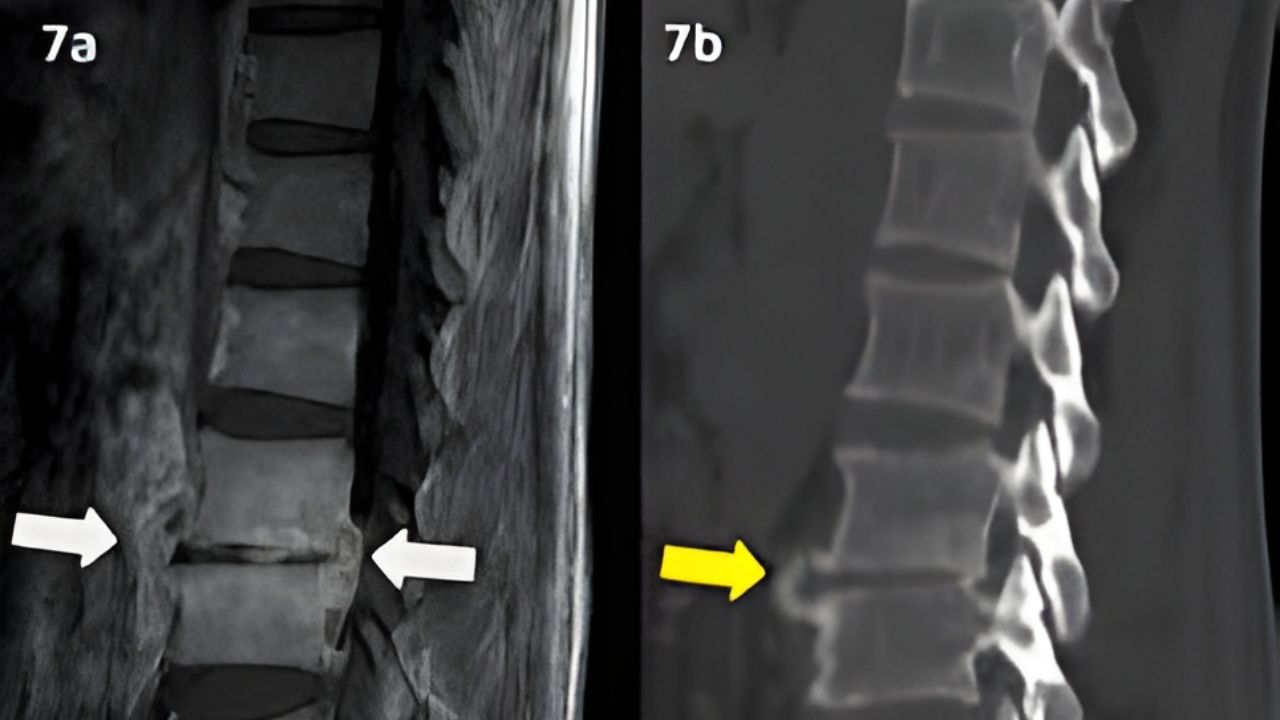

Exames de imagem como raio-x, ressonância magnética e tomografia são os mais utilizados para confirmar o diagnóstico.

Atuação em hérnia de disco, fraturas da coluna, escoliose, estenose vertebral e processos degenerativos.